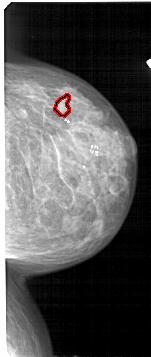

FILE: A_1713_1.RIGHT_MLO.OVERLAY

TOTAL_ABNORMALITIES 1

ABNORMALITY 1

LESION_TYPE CALCIFICATION TYPE PLEOMORPHIC DISTRIBUTION CLUSTERED

ASSESSMENT 4

SUBTLETY 1

PATHOLOGY BENIGN

TOTAL_OUTLINES 1

BOUNDARY